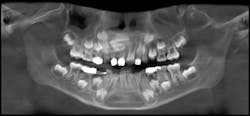

Patient: 7-year-old male

- Radiolucency appeared to focalize around the coronal portion of no. 7

- Ill-defined radiopacity within the osseous tissue under the area where primary tooth D would be located

- Not tender to palpation and no expansion in the vestibular area

- Patient had experienced trauma to the area a few years back while playing

Patient: 6-year-old male

- Tooth no. 9 had erupted normally after exfoliation of tooth F, but tooth E was still present

- Chief concern: Permanent teeth in the areas of nos. 7 and 8 might not be developing.

- Large radiodense area in the region apical to teeth D and E

- Otherwise healthy patient